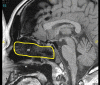

Objectives Bilateral anterior skull base (ASB) defects following endoscopic endonasal tumor resection are most commonly repaired utilizing multilayered reconstruction with a vascularized mucosal flap. Single-layer closure of large ASB defects has been described in the literature but this technique has yet to gain a widespread use. We report our experience with a series of patients who underwent reconstruction of large ASB defects using a single-layer intradural graft, without nasoseptal flaps. We also compared the use of acellular dermal matrix (AlloDerm, LifeCell, Branchburg, New Jersey, United States) or collagen matrix xenograft (Duramatrix, Stryker, Kalamazoo, Michigan, United States) as the graft biomaterial. Design A retrospective case series. Setting Tertiary academic medical center. Main Outcome Measures Postoperative cerebrospinal fluid leak, the number of postoperative debridements, the number of postoperative infections, and time to remucosalization. Results Two patients were reconstructed with AlloDerm and three with Duramatrix, with all patients receiving postoperative external beam radiation. There were no postoperative cerebrospinal fluid leaks identified in these patients during follow-up. The AlloDerm group showed increased postsurgical crusting, the number of clinically apparent postoperative infections, and an increased time to remucosalization. Conclusions Single-layer repair without a vascularized mucosal flap is a viable method of skull base repair for large ASB defects. We found repair with Duramatrix was superior, with less graft crusting and infection, requiring fewer debridements.